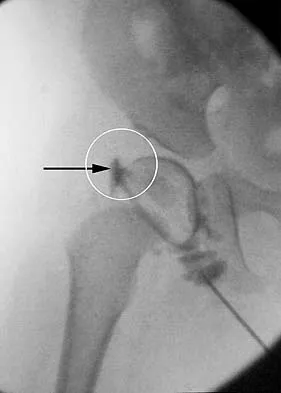

Question 43

Figure 36 shows the hip arthrogram of a newborn. Which of the following structures is enclosed by the circle?